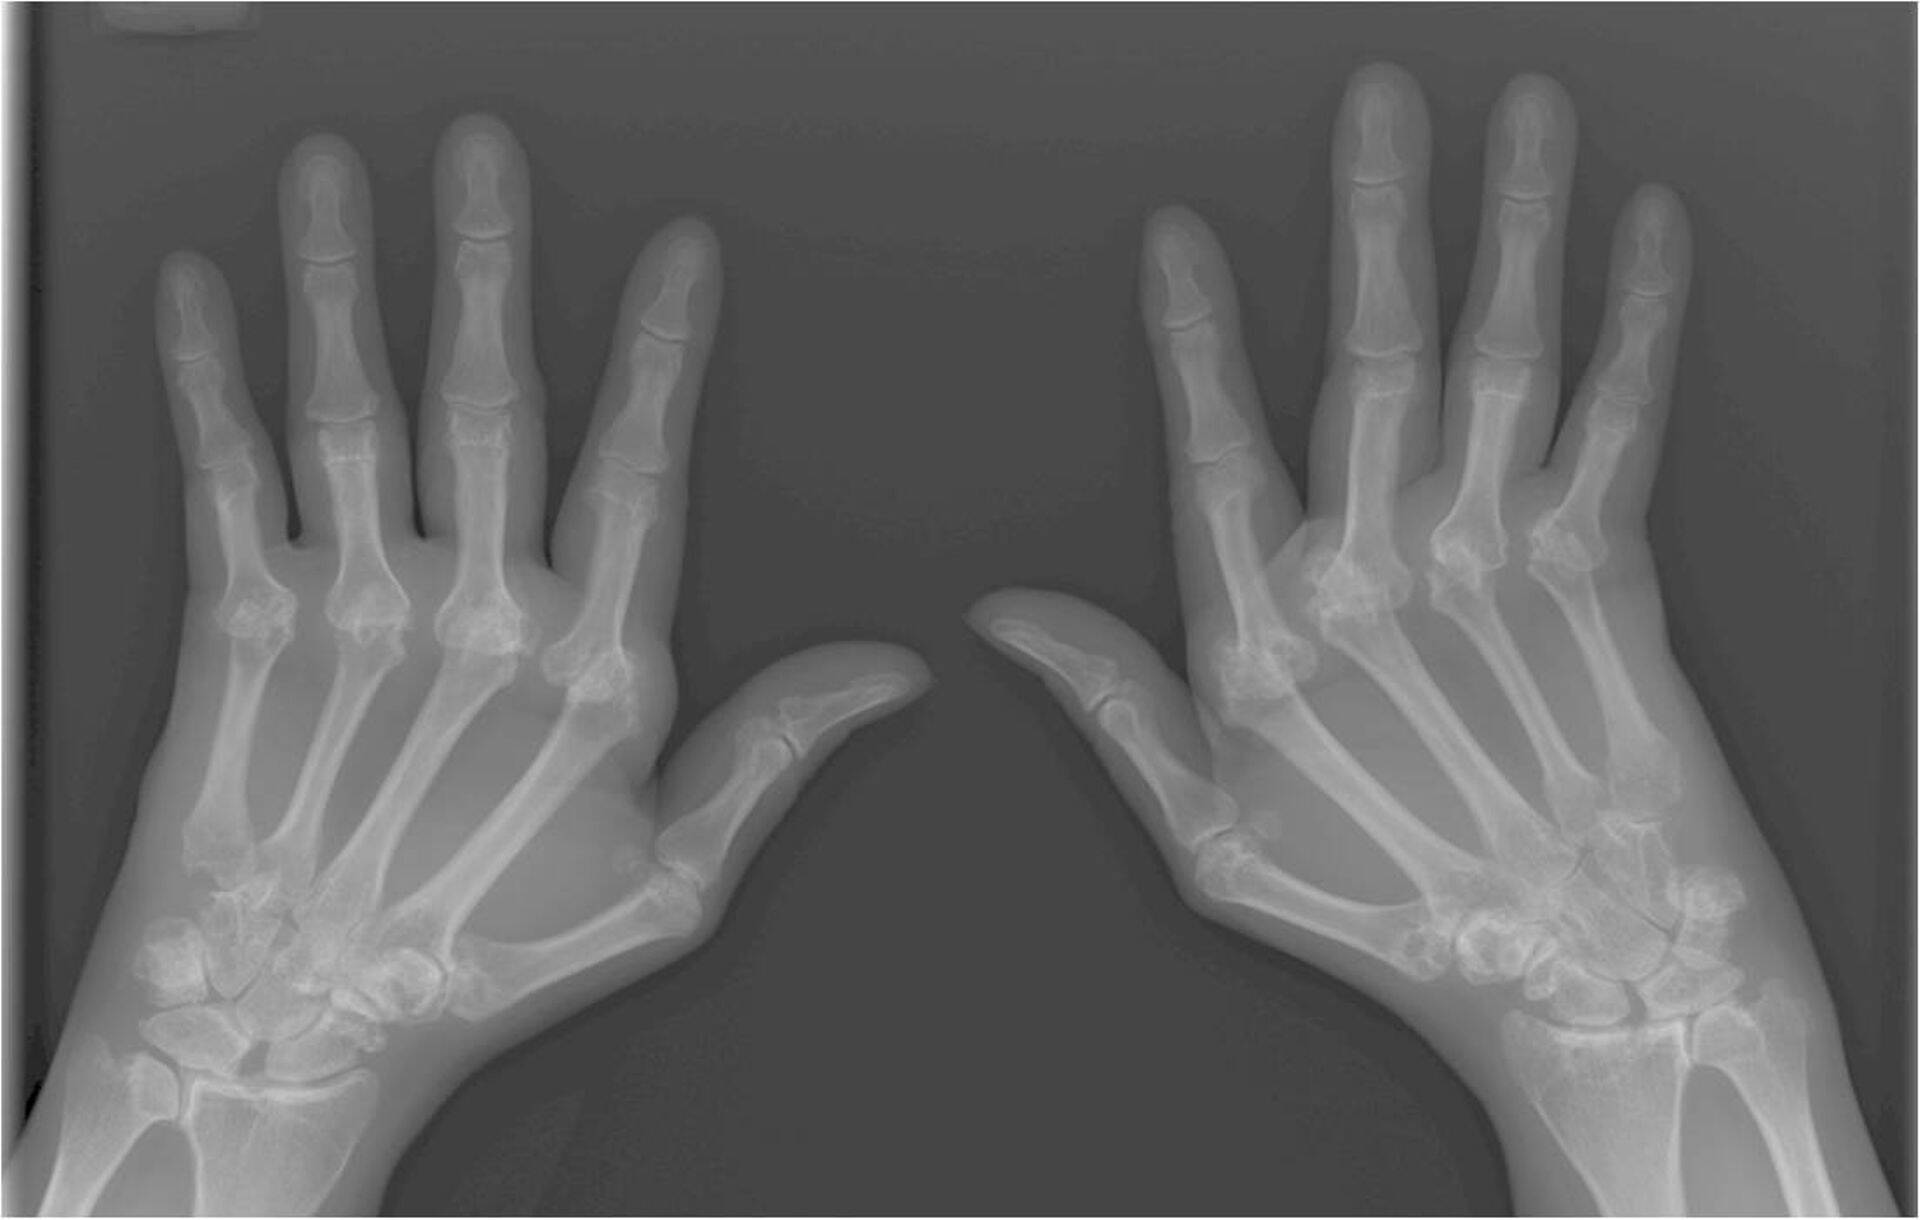

Reumatoidartriit (RA) on krooniline pidevalt edasiarenev, sageli invaliidistav hulgiliigesepõletik. Haiguse korral võivad olla haaratud ka liigeselähedased koed nagu limapaunad, kõõlustuped, lihased. RA võib kahjustada kõiki liigeseid. Tüüpiline on mõlema kehapoole liigeste sümmeetriline haigestumine.

- RA kõverad luud

Alati on RA-sse haigestumisel tabatud labakäte ja labajalgade liigesed (sõrmede ja varvaste tüviliigesed ning randmed), sageli põlve- ja õlaliigesed. Kauakestnud haigus võib kahjustada ka lülisammast, kus muutused toimuvad enamasti kaelaosas.